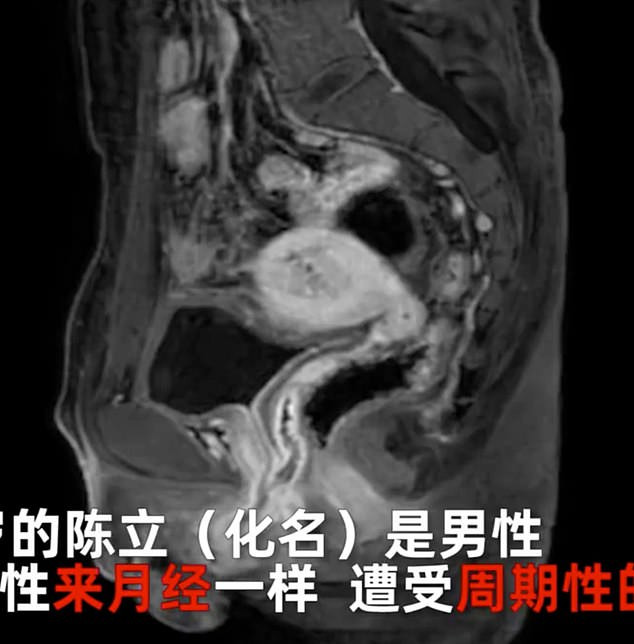

Vấn đề Chen gặp phải là có máu trong nước tiểu và bị đau bụng hằng tháng. Sau khi khám, các bác sĩ thông báo Chen được sinh ra với nhiễm sắc thể giới tính nữ (X) cũng như có buồng trứng và tử cung dù vẫn sở hữu cơ quan sinh dục nam.

Ban đầu, các bác sĩ còn chẩn đoán Chen bị viêm ruột thừa. Cho đến năm ngoái, họ mới tìm ra nguyên nhân khiến người đàn ông này bị đau bụng hằng tháng là do... có kinh nguyệt.

Chen được xác định là người liên giới tính, sở hữu nhiễm sắc thể X và cơ quan sinh sản nữ. Vào ngày 6-6 năm nay, Chen trải qua ca phẫu thuật kéo dài 3 giờ loại bỏ buồng trứng và tử cung. Bác sĩ phẫu thuật Luo Xiping nói với South China Morning Post rằng bệnh nhân "nhanh chóng tìm lại sự thoải mái và tự tin" sau ca phẫu thuật thành công.